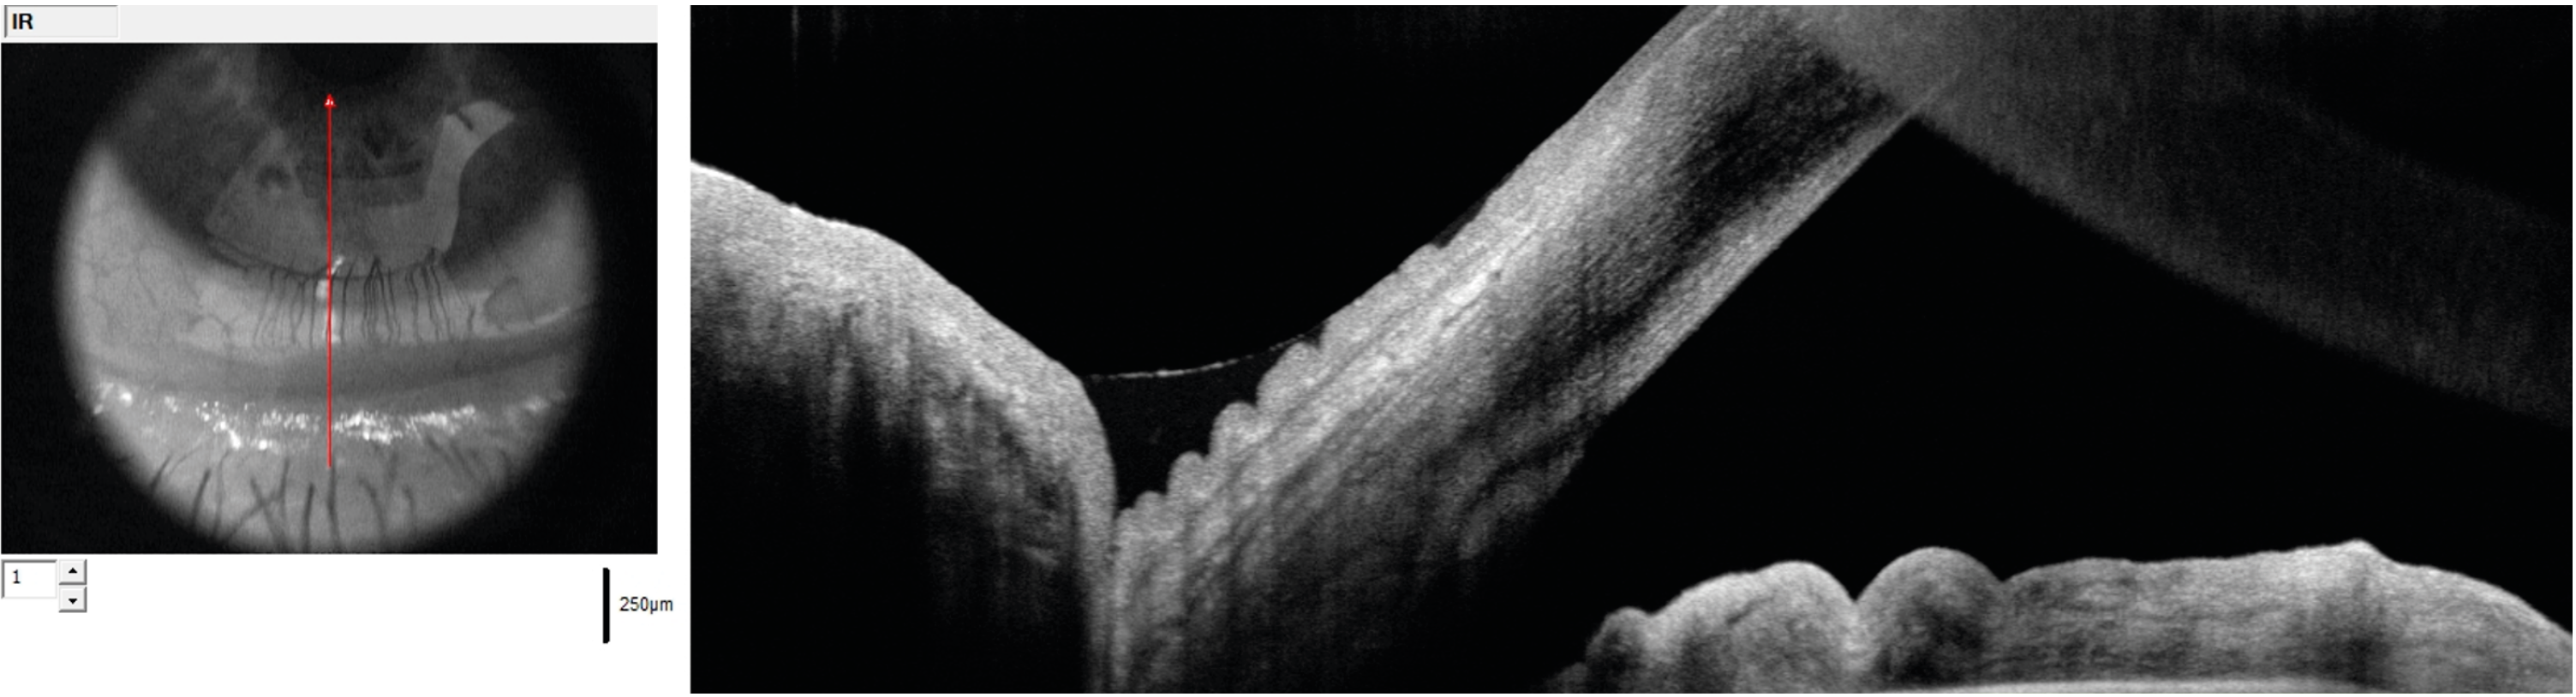

Figure 2. Schisis maculaire myopique en imagerie OCT ultra grand champ objectivant l’adhérence pathologique du vitré, avec des tractions exercées sur les vaisseaux rétiniens (tête de flèche), et l’étirement de la rétine externe maculaire associé à un détachement fovéolaire (flèche).